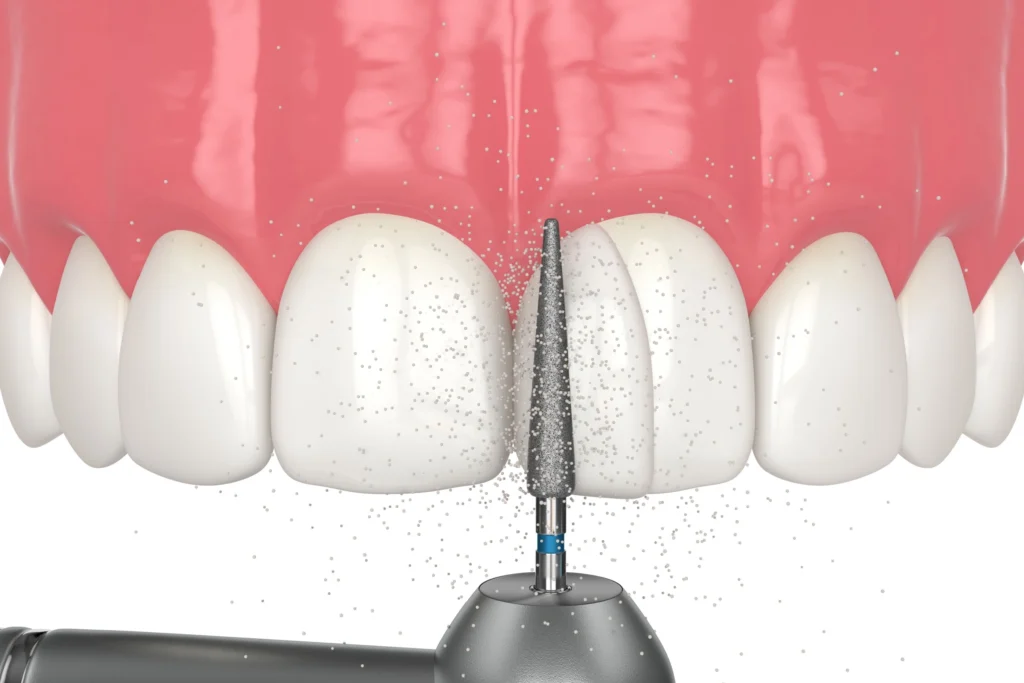

کامپوزیت دندان ماده ای هم رنگ دندان است که برای ترمیم و زیبایی دندان به کار می رود و می تواند تغییرات ظاهری و عملکردی مثبتی ایجاد کند. این ماده به صورت ونیر کامپوزیت یا پر کردن مستقیم روی دندان اعمال می شود و با تابش نور مخصوص سخت می گردد تا دوام کافی پیدا کند. استفاده از کامپوزیت دندان در کاشان توسط دندان پزشکان طراحی لبخند زیبا، به خصوص برای اصلاح لبخند، ترمیم شکستگی های جزئی و پوشاندن تغییر رنگ ها، بسیار متداول است. با انتخاب صحیح نوع کامپوزیت و روش مناسب، می توان نتیجه ای طبیعی و ماندگار به دست آورد، اما درک محدودیت های آن پیش از اقدام ضروری است.

ونیر کامپوزیت یکی از رایج ترین کاربردهای کامپوزیت دندان است که برای بهبود ظاهر دندان ها استفاده می شود. این روش به ویژه برای پر کردن فواصل بین دندان ها، اصلاح شکل نامناسب یا تغییر رنگ دندان های زرد یا لکه دار کاربرد دارد. به عنوان مثال، فردی که دندان های جلویی کمی نامنظم یا با لکه های کوچک دارد، می تواند با استفاده از ونیر کامپوزیت در مدت زمان کوتاهی لبخندی یکنواخت و طبیعی ایجاد کند. مزیت اصلی این روش، حداقل تراش مینای دندان نسبت به لمینت دندان است که باعث می شود فرآیند کمتر تهاجمی باشد و حساسیت کمتری ایجاد شود.